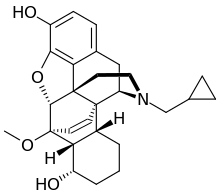

Oripavine derivatives

Thienorphine

- 7-PET

- Acetorphine

- Alletorphine (N-allyl-noretorphine)

- BU-48

- Buprenorphine

- Buprenorphine-3-glucuronide

- Cyprenorphine

- Dihydroetorphine

- Etorphine

- Homprenorphine

- 18,19-Dehydrobuprenorphine (HS-599)

- N-cyclopropylmethylnoretorphine

- Nepenthone

- Norbuprenorphine

- Norbuprenorphine-3-glucuronide

- Thevinone

- Thienorphine

Structures

| Oripavine derivatives | ||||

7-PET 7-PET |

Acetorphine Acetorphine |

Alletorphine Alletorphine |

BU-48 BU-48 |

Buprenorphine Buprenorphine |

Cyprenorphine Cyprenorphine |

Dihydroetorphine Dihydroetorphine |

Etorphine Etorphine |

Homprenorphine Homprenorphine |

18,19-Dehydrobuprenorphine 18,19-Dehydrobuprenorphine |

N-cyclopropylmethylnoretorphine N-cyclopropylmethylnoretorphine |

Nepenthone Nepenthone |

Norbuprenorphine Norbuprenorphine |

Thevinone Thevinone |

Thienorphine Thienorphine |